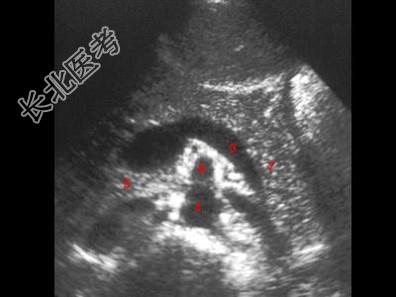

- 单项选择题图示5所指部位为   (   )

A、下腔静脉

B、胰头

C、腹主动脉

D、脾静脉

E、肠系膜上静脉